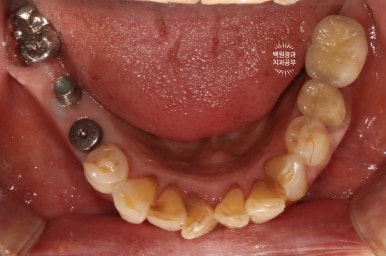

좌측은 위턱 사진, 오른쪽은 아래턱 구강내 사진입니다.

아주 어렵지 않게 두 치아가 부러져 있다는 것을 확인할 수 있죠.

아래 또한 깔끔하고 예쁘게 임플란트 크라운이 제작되었어요. 특징이라면 기존의 임플란트와 보철물을 묶어서 제작해드림으로써 음식이 끼는 것을 확실히 막아드렸다는 것입니다!